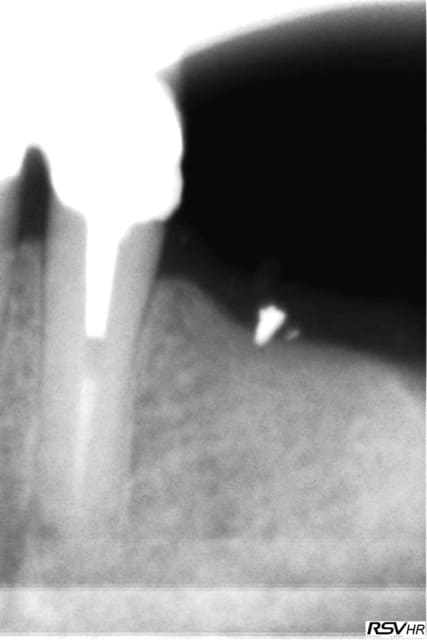

sinon le deuxième site, moi, me paraît louche...c'est pas du D4, j'aurais plutôt tendance à dire que c'est du tissu de granulation...( et peut être bien un petit morceau de racine...c'est pas très net...)

une racine le morceau en distal e je l'ai enleve avant le scan, la radio date du 21.1 et le scan du 14.3.... je ne pense pas avoir de pano d'ensemble post extractionnel.

Maintenant lors de l'exam clinique il ne m a pas semble voir de tissus bourgeonnant comme on peut le voir lorsqu'il reste du tissu de granulation mais je peux me tromper.

Si c'est du TG quelle conduite à tenir???

oui, donc tu es à 8 semaines post extraction pour ton scan...c'est un peu juste pour juger de la densité osseuse, non?

au mieux tu es dans de l'ostéoïde...sinon dans du TG...

le problème: tu es limite en hauteur, et si tu es dans du mou, çà va pas vraiment le faire pour trouver une stab primaire...

et non pas à 8 semaines je l'ai extraite le 19.11.2011 donc c'est plus et je te joins une retro avant l'extraction la dent ne présentais pas de lésion paro enorme donc je ne vois pas pourquoi un TG se serait développé plus facilement.

J'ai du utiliser un fraise zekrya et j'ai mis dans l'aveole des éponges hémostatiques collageniques.

c'est pas parce que t'as mis des éponges que tu n'as pas eu une petite alvéolite qui a retardé la cicat (chose fréquente quand on utilise une fraise pour faire une alvéolectomie/séparation...)

à 4 mois amha çà devrait être plus dense si tout était normal...